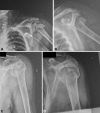

Background: Four-part fractures of the proximal humerus account for 3% of all humeral fractures and are regarded as the most difficult fractures to treat in the elderly. Various authors recommend nonoperative treatment or hemiarthroplasty, but the literature is unclear regarding which provides better quality of life and function.

Figures